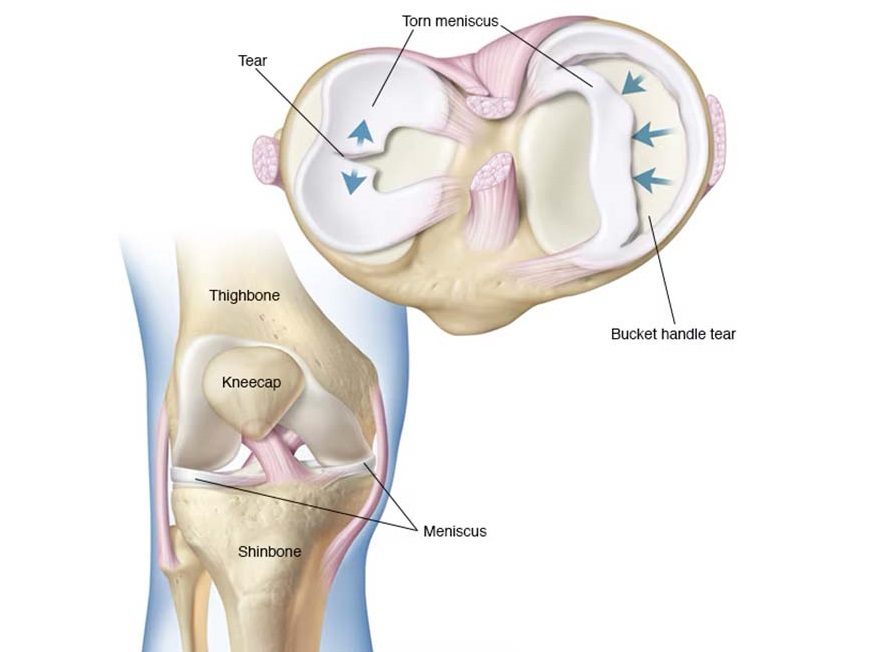

Meniscus Tear

Meniscus Tear Causes, Symptoms, and Treatment A meniscus tear is a common knee injury that occurs when…